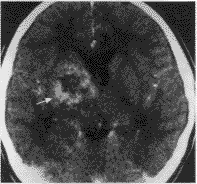

二、囊变、坏死与出血: 11例中5例肿瘤内可见囊变、坏死灶。CT图像上表现为水样低密度影(图1,2),MR上则为混杂性长T1和长T2信号影(图3,4)。9例经MR检查者,T1加权像4例见肿瘤内有斑块样出血灶,表现为不规则形斑块样高信号强度影(图3)。

三、增强类型: 静脉注入对比剂后,9例表现为斑块样或斑片样增强(图5),1例为环形增强,1例为环形分隔样增强。

图3~5 右侧基底节生殖细胞瘤。T1加权像(图3)和T2加权像(图4)见肿瘤信号不均匀,并可见出血灶(箭头),增强扫描(图5) 见肿瘤为斑片样增强(双箭头)